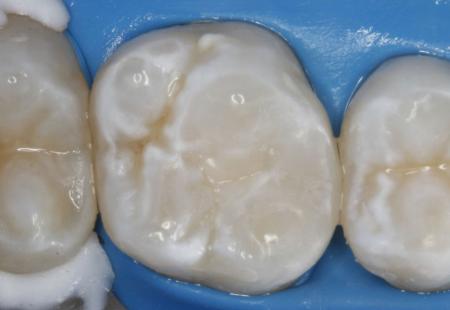

1.7 и 1.6 зубы – Эстетические реставрации под микроскопом с применением техники «Силиконового ключа»